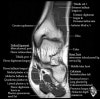

발목 관절의 MRI 단면 영상

- Sagittal section

Bones and marrow

Joint fluid

Talar dome

Subtalar joints

Achille's tendon

Sinus tarsi

Plantar fascia